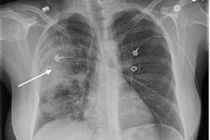

Viêm phổi mắc phải cộng đồng là bệnh lý nhiễm trùng phổi do sự tấn công của các tác nhân gây bệnh mắc phải trong cộng đồng. Bệnh không được điều trị tích cực rất dễ trở nặng và gây các biến chứng tại chỗ hoặc toàn thân.